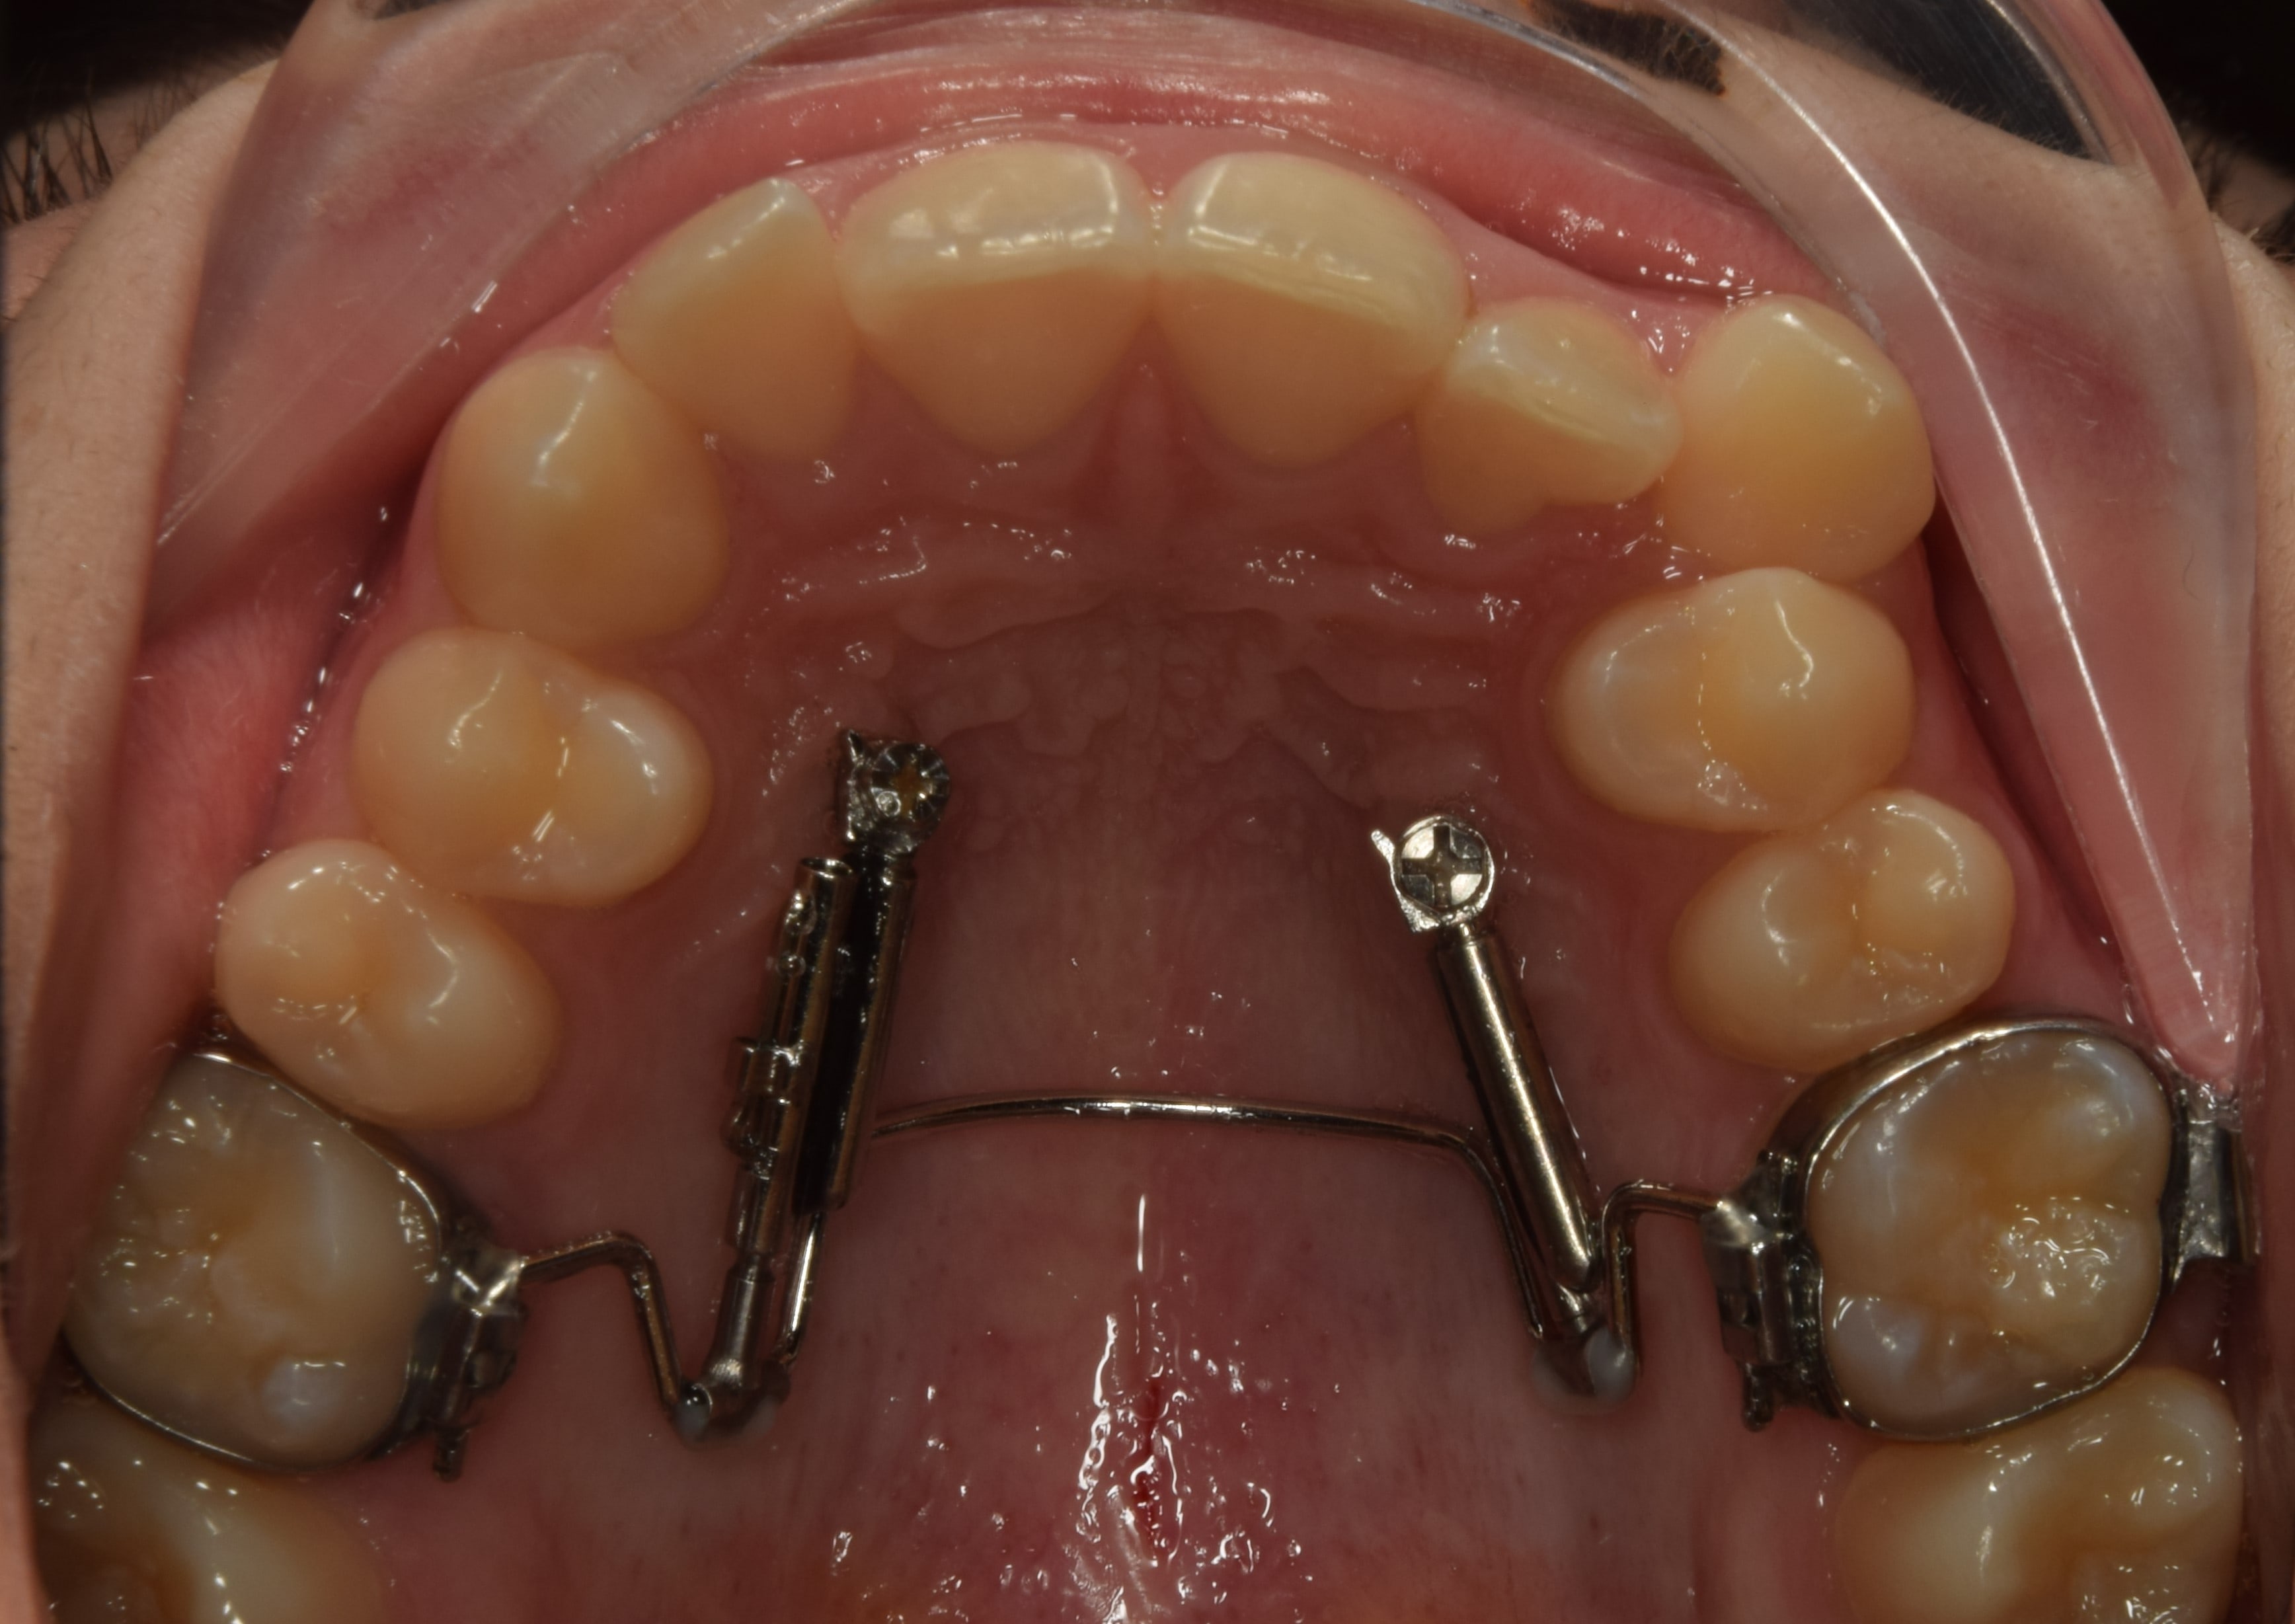

Blue grass

A felső első őrlőfogakon gyűrűvel rögzülő, a szájpadot vékony acélívvel áthidaló rögzített fogszabályzó készülék, mely közepén (a szájpadon) apró golyó található. Ezt a golyót nyelvvel pörgetni lehet, ezért gyerekeknél gyakran használjuk használjuk nyelvlökéses nyelés korrekciójára. A készülékkel játékosan érhető el a nyelv helyes pozícióba szoktatása.

A kép forrása: https://kieferorthopaedie.com/